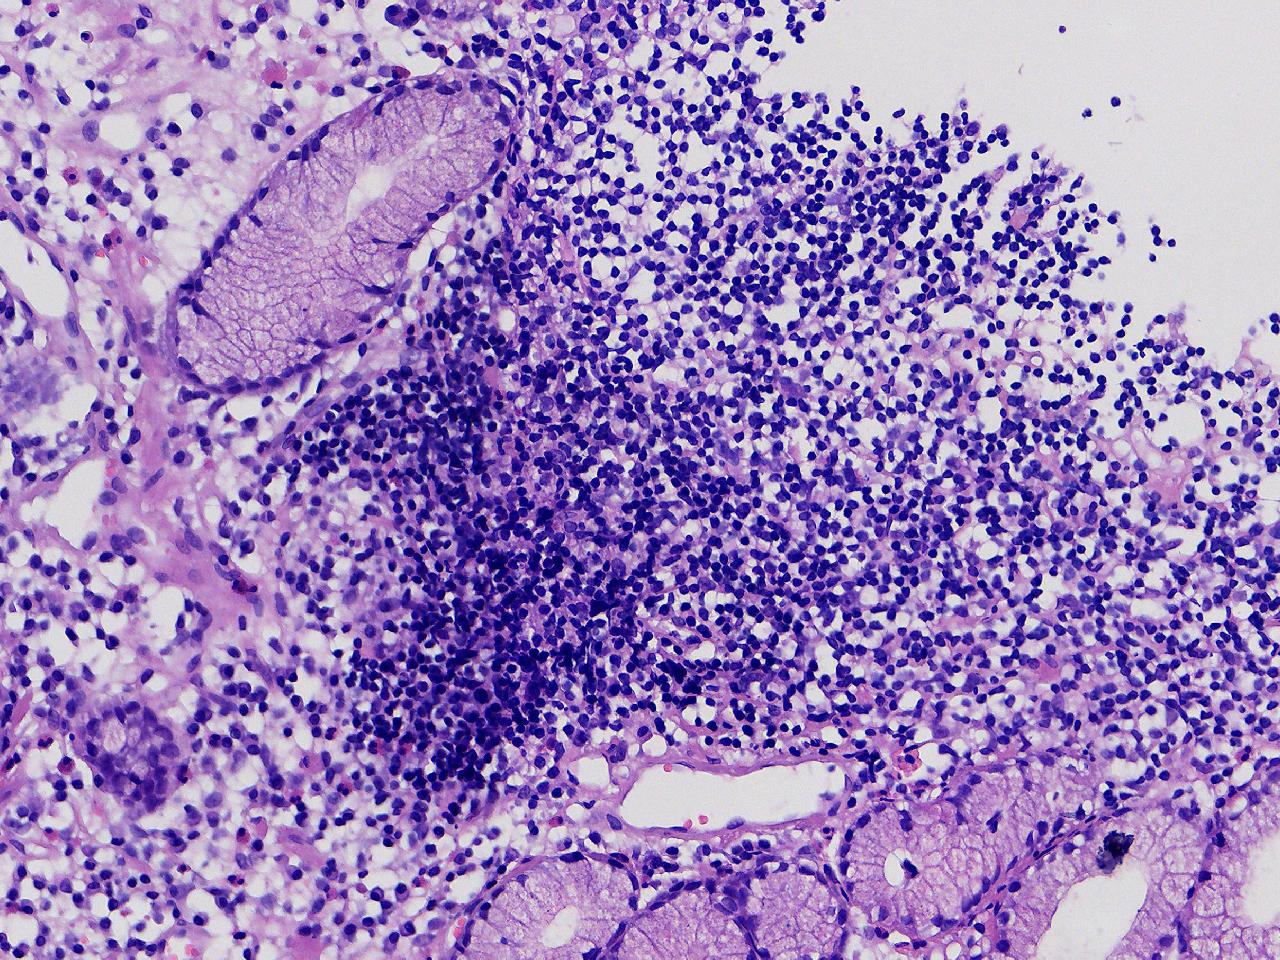

男,76岁。胃体前壁见1纵行溃疡,底覆白苔,周围粘膜充血水肿,于病变周边取材3块。

胃体前壁活检

灰白色不整形软组织3块,直径均0.2厘米。

粘膜中度慢性炎伴糜烂,固有层淋巴细胞聚集